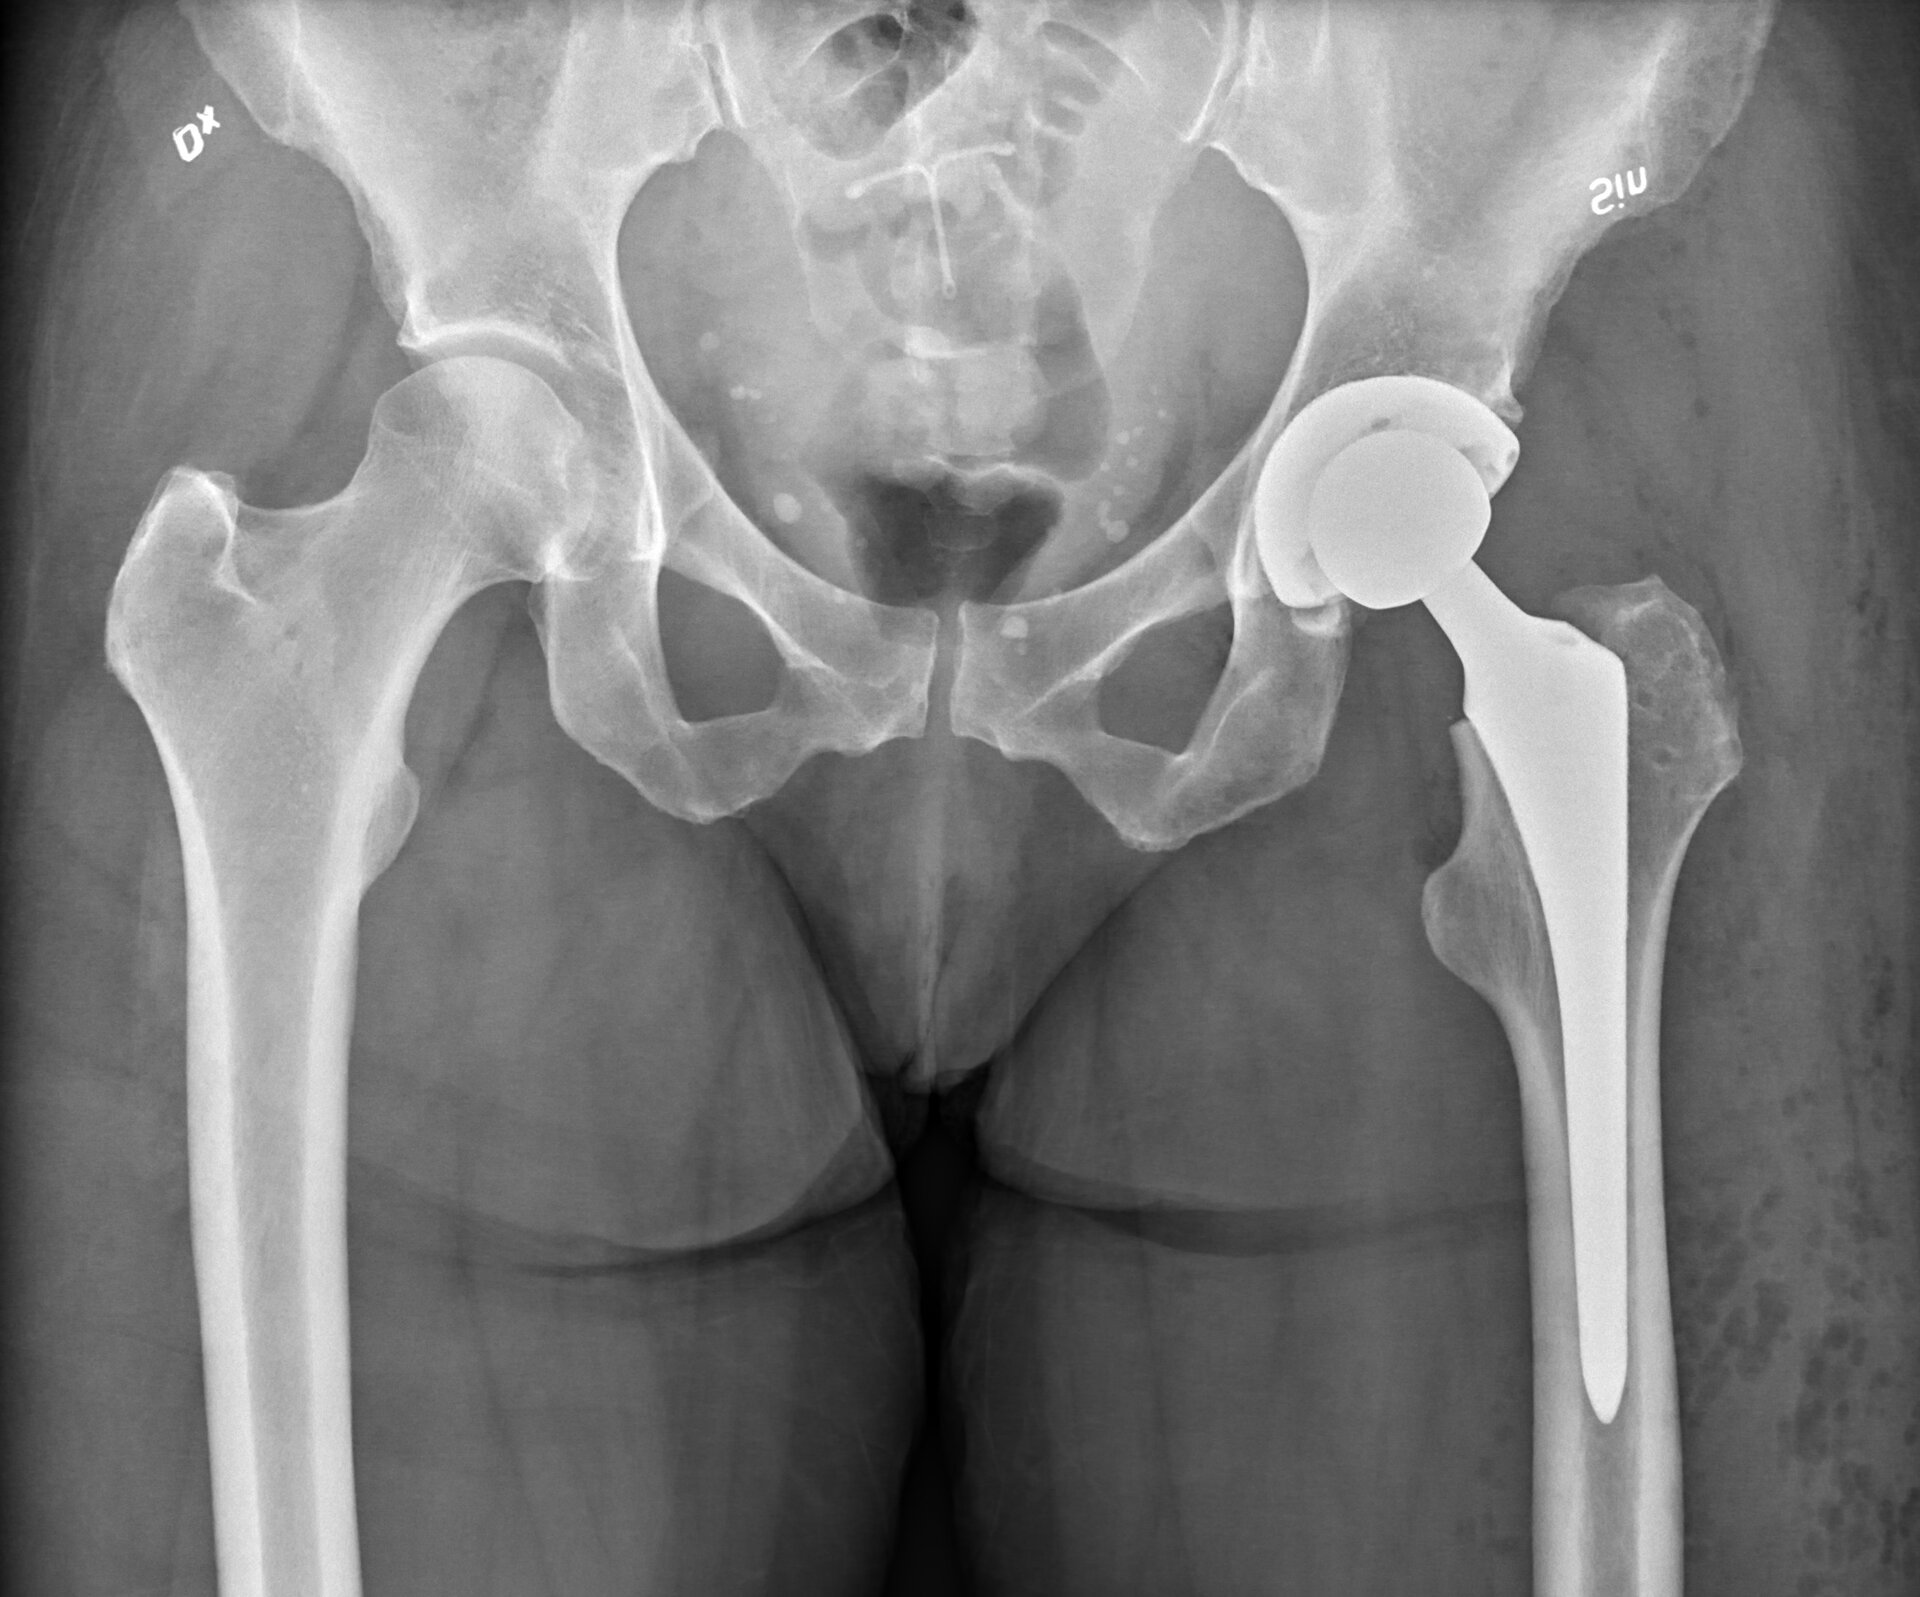

Trwałymi organicznymi związkami krzemu są np. silikony. Dzięki ich właściwościom hydrofobowymhydrofobowym są nieaktywne biologicznie i wykorzystywane w medycynie, np. jako protezy stawów.